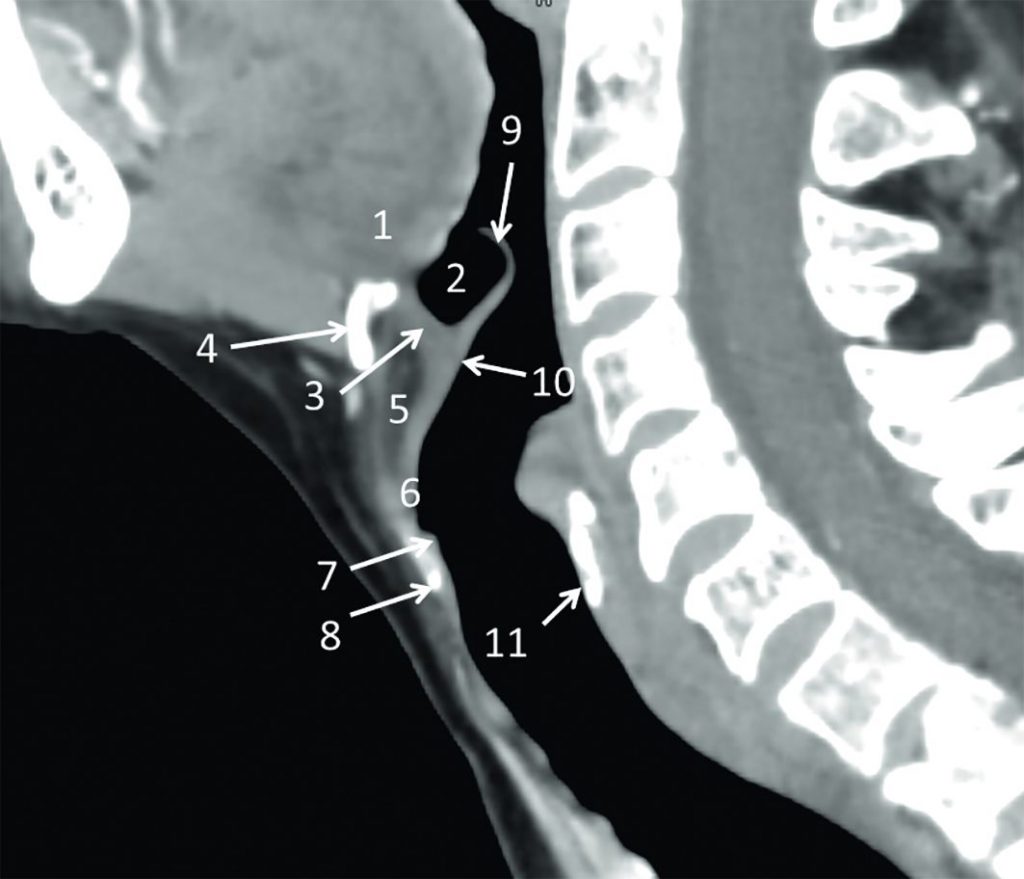

Fig. 62.8 Cou : scanner, coupe sagittale.

1. Base de la langue. 2. Vallécule épiglottique. 3. Membrane hyo-épiglottique. 4. Os hyoïde. 5. Loge pré-épiglottique (loge hyo-thyro-épiglottique). 6. Pied de l’épiglotte et ligament thyro-épiglottique. 7. Commissure antérieure de la glotte. 8. Cartilage thyroïde. 9. Bord libre de l’épiglotte. 10. Face laryngée de l’épiglotte. 11. Cartilage cricoïde.